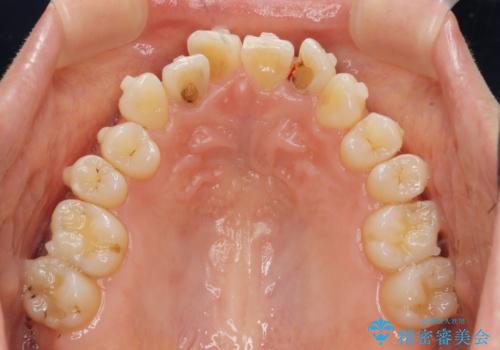

前歯の目立つガタつきをマウスピース矯正で治療

- 大きく傾いてしまった前歯のガタつきの改善を求めて来院されました。

前歯のガタつきをしっかりと取り、機能的・審美的に理想的な歯並びをマウスピース矯正で達成します。

強度のガタつきはマウスピース単体では並び切ることが難しいこともありますが、しっかりと装着していただいたことで良好な治療結果を得ることができました。